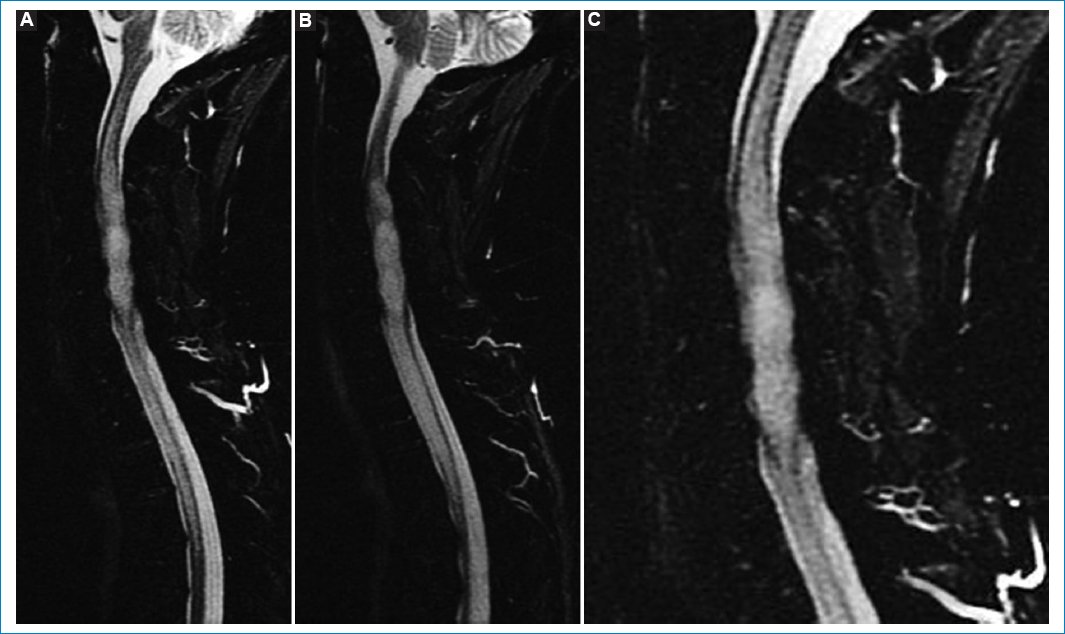

Figura 1. RM sagital ponderada en T2. Muestra aumento del tamaño de la médula espinal con centro de hiperintensidad intramedular difusa de extensión longitudinal, compatible con infiltración tumoral con centro quístico: cortes contiguos (A y B) y ampliación de A (C).

Figura 3. Secuencia STIR. (A) Corte central. (B) Corte contiguo. (C) Ampliación de A. Hiperintensidad extensa y homogénea de la médula espinal afectada que excede el volumen tumoral sólido que se verá en la secuencia ponderada en T1.

Figura 4. (A) Secuencia sagital ponderada para T1 sin contraste. (B) Secuencia sagital STIR después de administrar contraste paframagnético. Tras la administración de gadolinio en secuencia STIR se observa realce periférico en anillo (rim enhancement).

Tiene una posición central con una porción quística intratumoral. La lesión es isointensa en T1 e hiperintensa en T2 y STIR (Figs. 15). Después de administrar contraste paramagnético endovenoso hay realce periférico, especialmente alrededor de la formación quística. Por debajo del polo inferior se ve siringohidromielia de corto trayecto. Las características de las imágenes coinciden con las descripciones que aparecen en la bibliografía35.